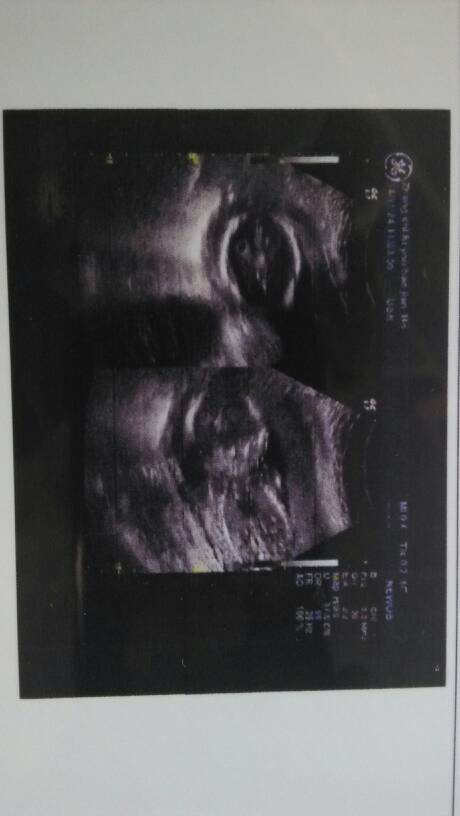

18加3检查胎儿双侧脉络丛囊肿,谁帮看看怎么办 18加3检查胎儿双侧脉络丛囊肿,谁帮看看怎么办 点击展开 →宝宝乖乖← 2014-11-24 12:41 为您推荐: 其他回答 不客气…… 〢﹎懂ㄋ這愛 2014-11-24 22:02 我更担心喔。 Angelia_CVgb 2014-11-24 21:51 我的比你大多了,毫米的 Angelia_CVgb 2014-11-24 21:50 嗯,加油! 159*****554_e99t 2014-11-24 21:34 我是查出脐带囊肿,好担心,希望我们都会平安度过 159*****554_e99t 2014-11-24 19:19 加载更多 相关问题 胎儿被检查出脉络丛囊肿怎么办? 18加3检查胎儿双侧脉络丛囊肿,谁帮看看怎么办 胎儿双侧脉络丛囊肿18周+3怎么办啊